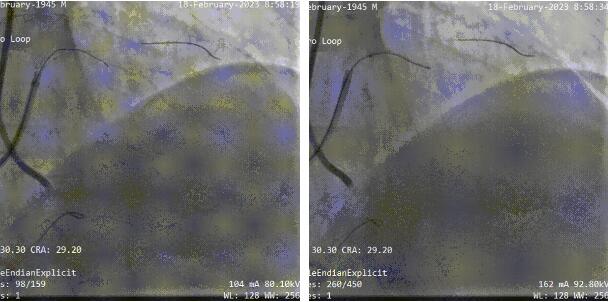

双侧造影结果:

依据3D打印指导+双侧造影,双腔微导管+UB3导丝一刻钟的时间左右成功通过CTO段到远端真腔: